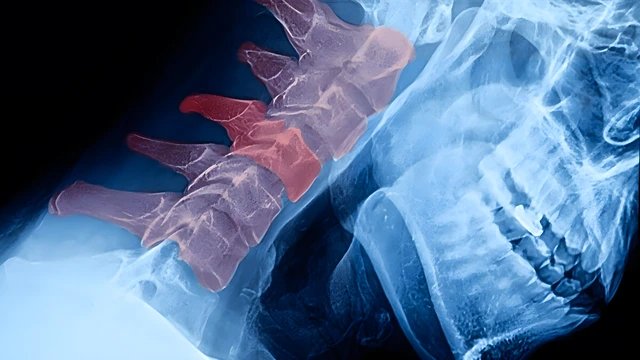

Thoát vị đĩa đệm cột sống cổ là tình trạng nhân nhầy của đĩa đệm thoát ra ngoài bao xơ, chèn ép lên rễ thần kinh hoặc tủy sống, gây ra đau nhức vùng cổ và vai gáy, kèm tê bì lan xuống cánh tay, bàn tay và các ngón tay, thậm chí có thể dẫn đến liệt nếu không được can thiệp kịp thời. Theo dõi bài viết dưới đây của Nhà thuốc Long Châu để tìm hiểu về vấn đề sức khỏe này.